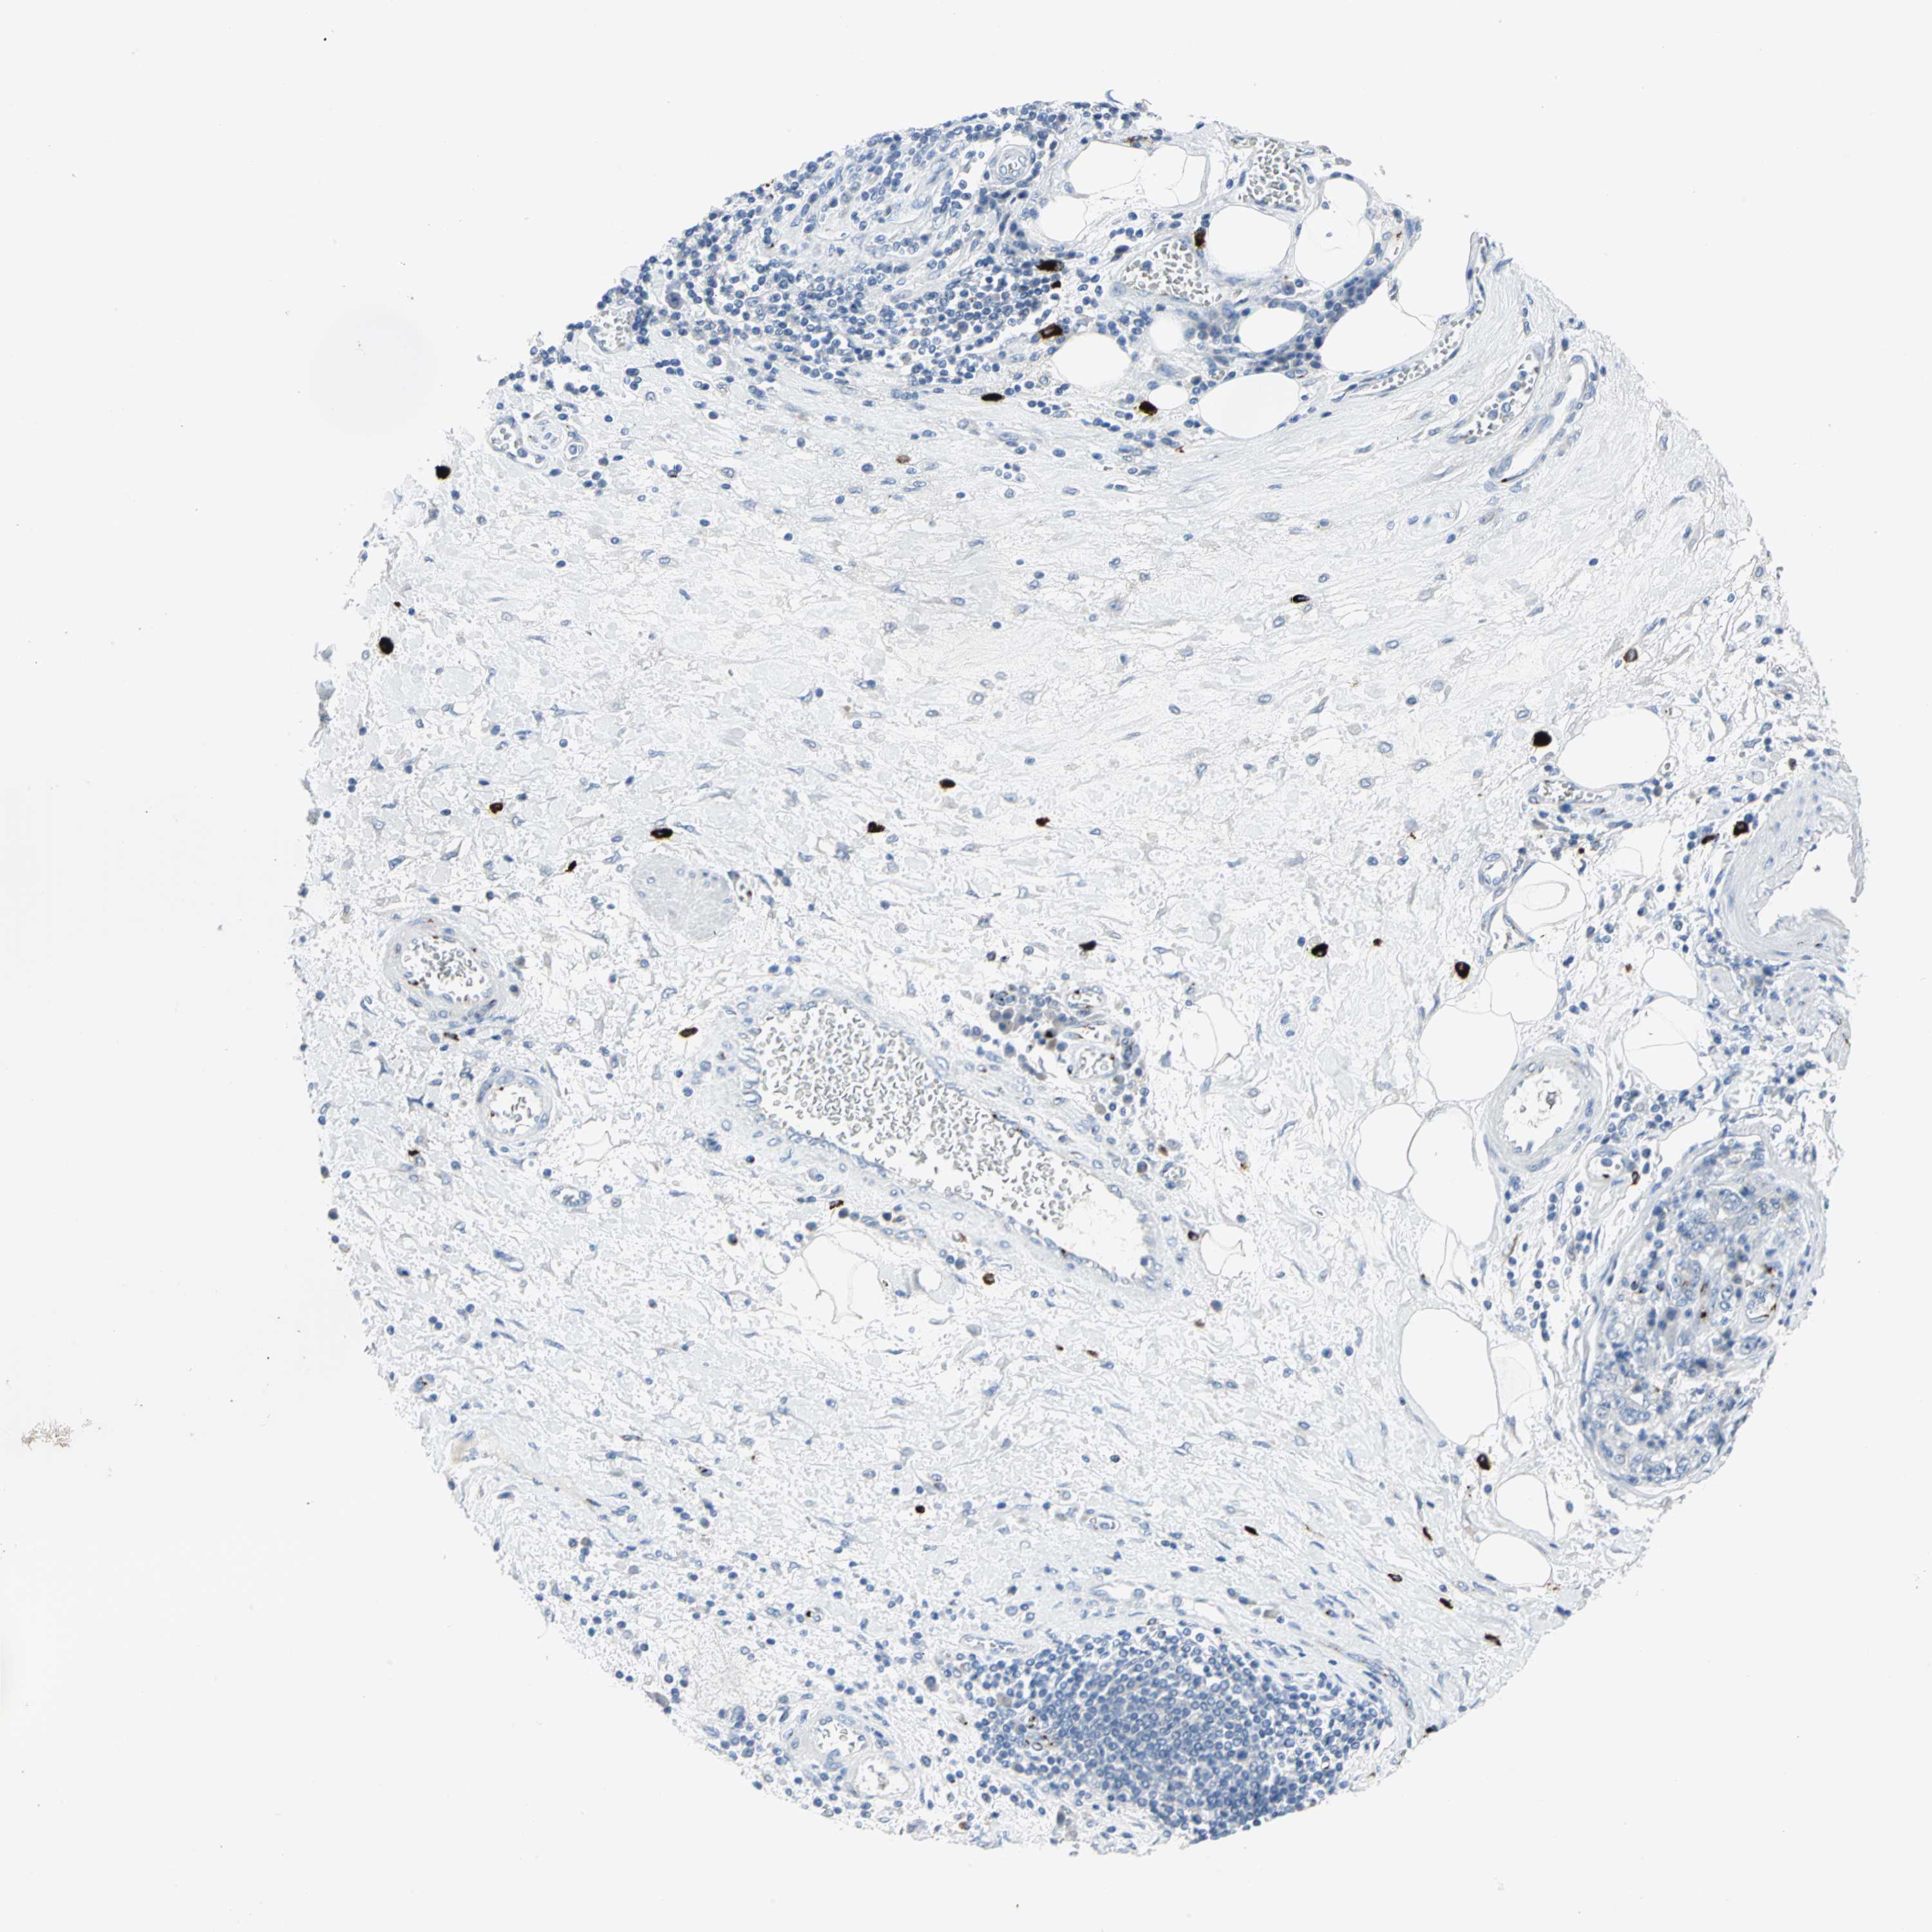

STOMACH CANCER - Protein expressioni

A mouse-over function shows sample information and annotation data. Click on an image to view it in a full screen mode. Samples can be filtered based on level of antibody staining by selecting one or several of the following categories: high, medium, low and not detected. The assay and annotation is described here.

Note that samples used for immunohistochemistry by the Human Protein Atlas do not correspond to samples in the TCGA dataset.

Antibody stainingi

Antibody staining in the annotated cell types in the current human tissue is reported as not detected, low, medium, or high, based on conventional immunohistochemistry profiling in selected tissues. This score is based on the combination of the staining intensity and fraction of stained cells.

Each image is clickable and will lead to virtual microscopy that enables deeper exploration of all samples and also displays staining intensity scores, fraction scores and subcellular localization as well as patient and tissue information for each sample.

Antibody CAB006254

Staining

High

Medium

Low

Not detected

Intensity

Strong

Moderate

Weak

Negative

Quantity

>75%

75%-25%

<25%

None

Location

Nuclear

Cytoplasmic/membranous

Cytoplasmic/membranous,nuclear

Adenocarcinoma, NOS

Adenocarcinoma, High grade